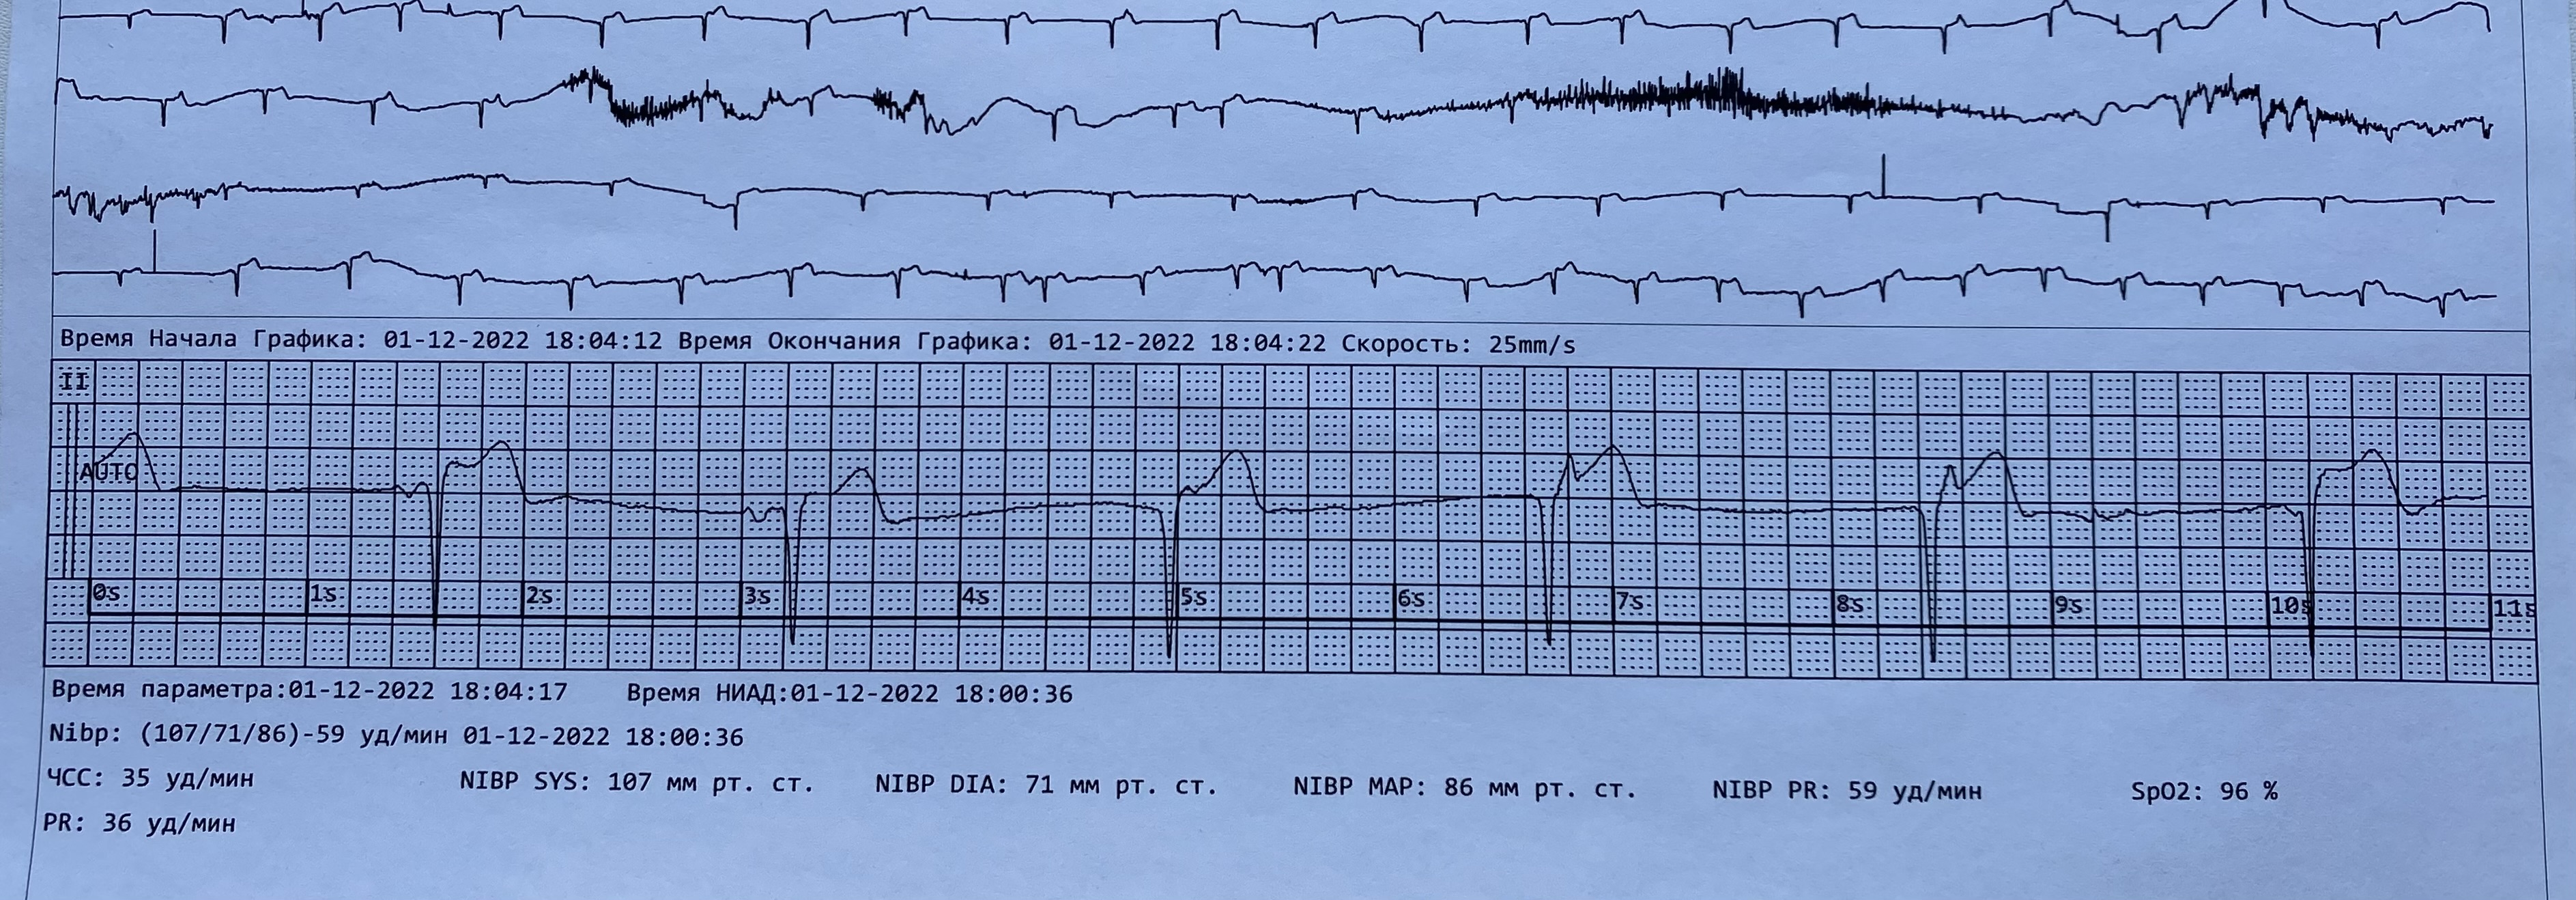

Не очень классически, но это МВР

Обсуждалось в Госпитале Ослабленных Сердец

3.JPG

3.JPG [ 1.44 MiB | Просмотров: 24383 ]

4.JPG

4.JPG [ 1.63 MiB | Просмотров: 24383 ]